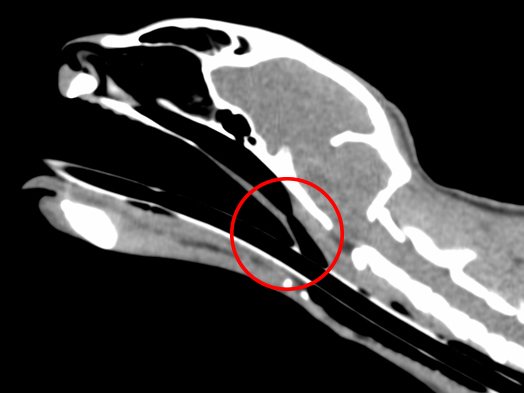

CT検査:赤丸が狭窄部位

約3ヶ月前より鼻炎症状を主訴に他院を受診し、鼻炎としての治療が行われたものの、十分な改善が見られなかったため、精査を目的として当院を受診されました。 当院にてCT検査を実施したところ、鼻咽頭部に顕著な狭窄を認めたことから、呼吸器症状の改善を目的に、鼻咽頭狭窄に対するバルーン拡張術を実施しました。 処置後の経過は良好で、全身状態も安定していたため当日退院としました。 その後も経過観察を継続しており、現在までに7ヶ月が経過しましたが、再発は認められていません。